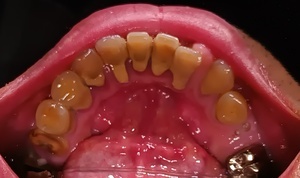

Before(歯石除去前)

下の前歯裏側にびっしりと付着した茶褐色の歯石が、歯間まで覆っています。表面が粗く、不衛生な印象を与えています。